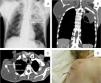

A 61-year-old man, smoker, with no significant previous medical history, was admitted to the respiratory medicine department with a 4-month history of right suprascapular swelling, progressively increasing in size, accompanied by intense local pain and limited mobility of the right upper limb. He reported asthenia and weight loss during the previous 4 months. He had no anorexia, fever, or respiratory complaints. Physical examination revealed marked weight loss, a suprascapular right mass of about 10cm, and decreased breath sounds were detected on lung auscultation. Blood analysis showed elevated systemic inflammatory markers. Chest X-ray (Fig. 1) revealed a dense soft tissue mass in the right scapula and a cavitating mass with an air-fluid level in the upper half of the left lung. Chest CT (Fig. 1) confirmed the presence of a bulky mass invading the right scapula and the adjacent muscles and a cavitating lung mass in the left upper lobe (see legend). Pathology examination of both lesions revealed a poorly differentiated squamous cell carcinoma of the lung with metastasis to contralateral soft tissues. During hospitalization, the patient's general condition deteriorated progressively and, despite optimal supportive care, the patient died later due to disease progression.

A–chest X-ray (posteroanterior incidence): mass with dense soft tissues in the right scapula, and a cavitation with fluid level in the upper half of the left lung. B and C–chest CT (coronal and axial planes): bulky heterogeneous mass of about 110×94mm invading the right scapula and the adjacent muscles, with periosteal reaction of the scapula, and heterogeneous nodular formation in the apical posterior segment of the left upper lobe, with central cavitation, of about 88×80mm, with invasion of the mediastinal fat and the chest wall. D–photography of suprascapular right mass after surgical biopsy.